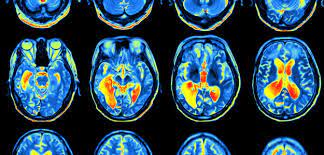

Music activates every area of the brain that we have so far mapped in fact there's no area of the brain that we know about that music doesn't touch in some way, but what's behind all that what exactly does music do to us?

25 years ago, the idea was that language is on the left side of the brain and music is on the right side of the brain but now that we've got better quality tools higher resolution neuroimaging, and better experimental methods, it is found that music is going on in both halves of the brain the left and the right, the front in the back the inside and the outside.

A musician, Fantastic Negrito was made to play one of his songs while going through fMRI; the result was the areas that process sensory and motor skills along sounds lit up.

But when he was asked to create something original, the areas that were active before, the ones that deal with motor skills and sounds are even more active.

As we could see more of the area of the prefrontal cortex which is associated with effortful planning and conscious self-monitoring is less active, it appears to be really shut down in these moments of high creativity like letting go of this conscious self-censoring or self-monitoring area that are normally there to help control that output.